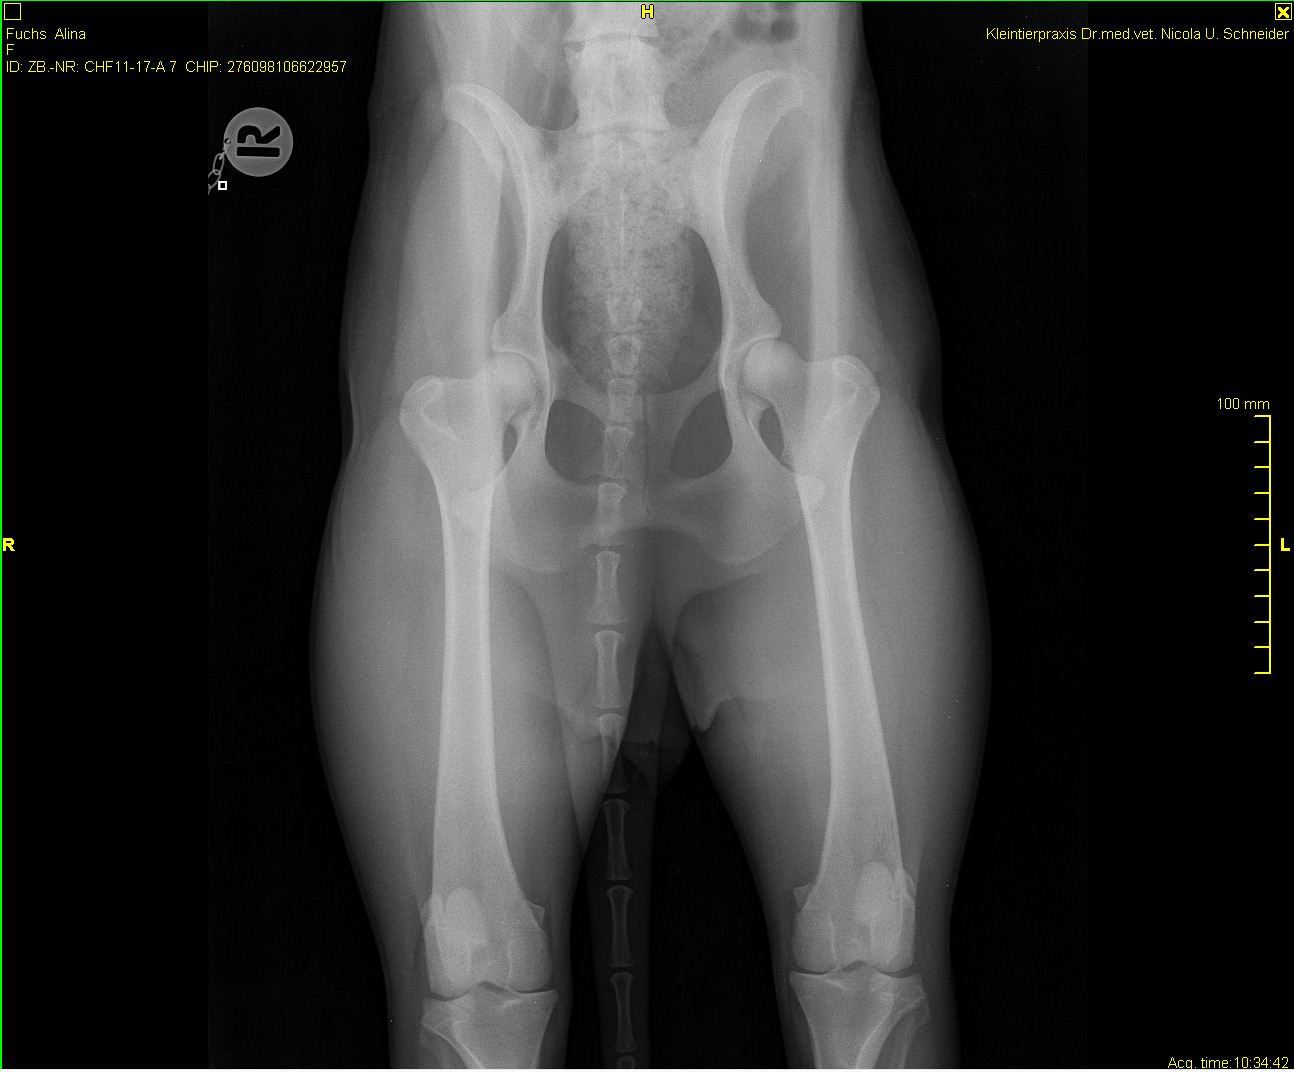

Alina - HD-Röntgen

-Alina hd